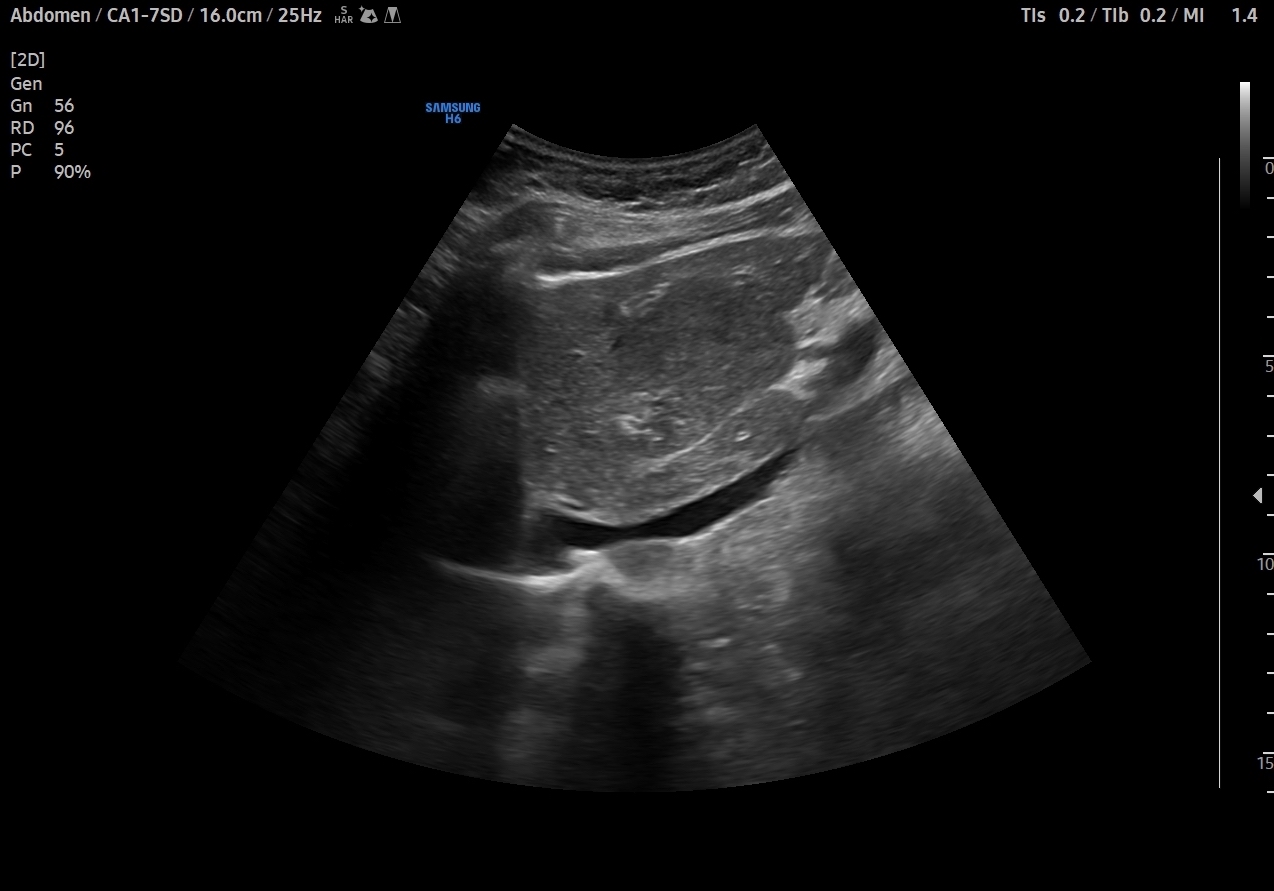

En el lóbulo hepático izquierdo visualizamos lesión focal iso-hipoecogénica respecto al parénquima hepático circundante que mide 4,6 x 4,5 x 3,9 cm y que presenta un aumento de la señal Doppler. Vemos la imagen tanto en cortes transversales como en cortes longitudinales, también con el modo Doppler activo. Resto de parénquima hepático y vía biliar de aspecto normal, sin otras alteraciones.

Dados los antecedentes de la paciente (edad y toma anticonceptivos orales) la imagen ecográfica inicial impresiona de hiperplasia nodular focal. El diagnóstico diferencial comprende otras lesiones focales en el hígado: hemangioma, adenoma, quiste, hepatocarcinoma, tumores metastásicos. En este caso la concordancia con la posterior RM hepática es total.